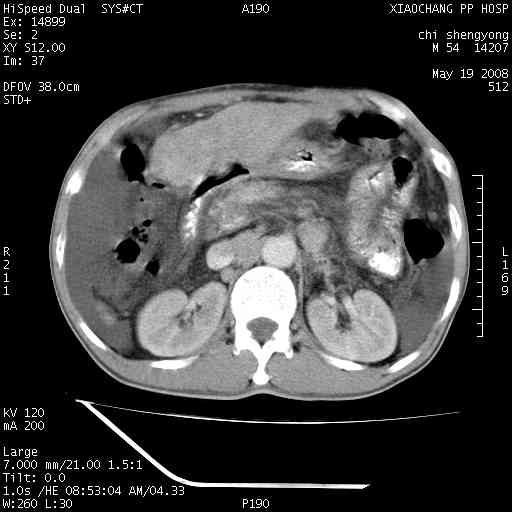

以下是引用zjzjr在2008-5-21 10:52:00的发言:[br]肝左叶巨块型肝癌伴门静脉左支瘤栓形成.肝硬化、腹水,胃底静脉曲张,脾术后改变。

以下是引用随光逐影在2008-5-21 16:20:00的发言:[br]1)肝左叶肝癌伴门静脉左支瘤栓形成,腹膜后淋巴结转移。2)肝硬化、腹水、胃底静脉曲张。3)胆囊炎。4)脾脏缺如,为切除术后所致。